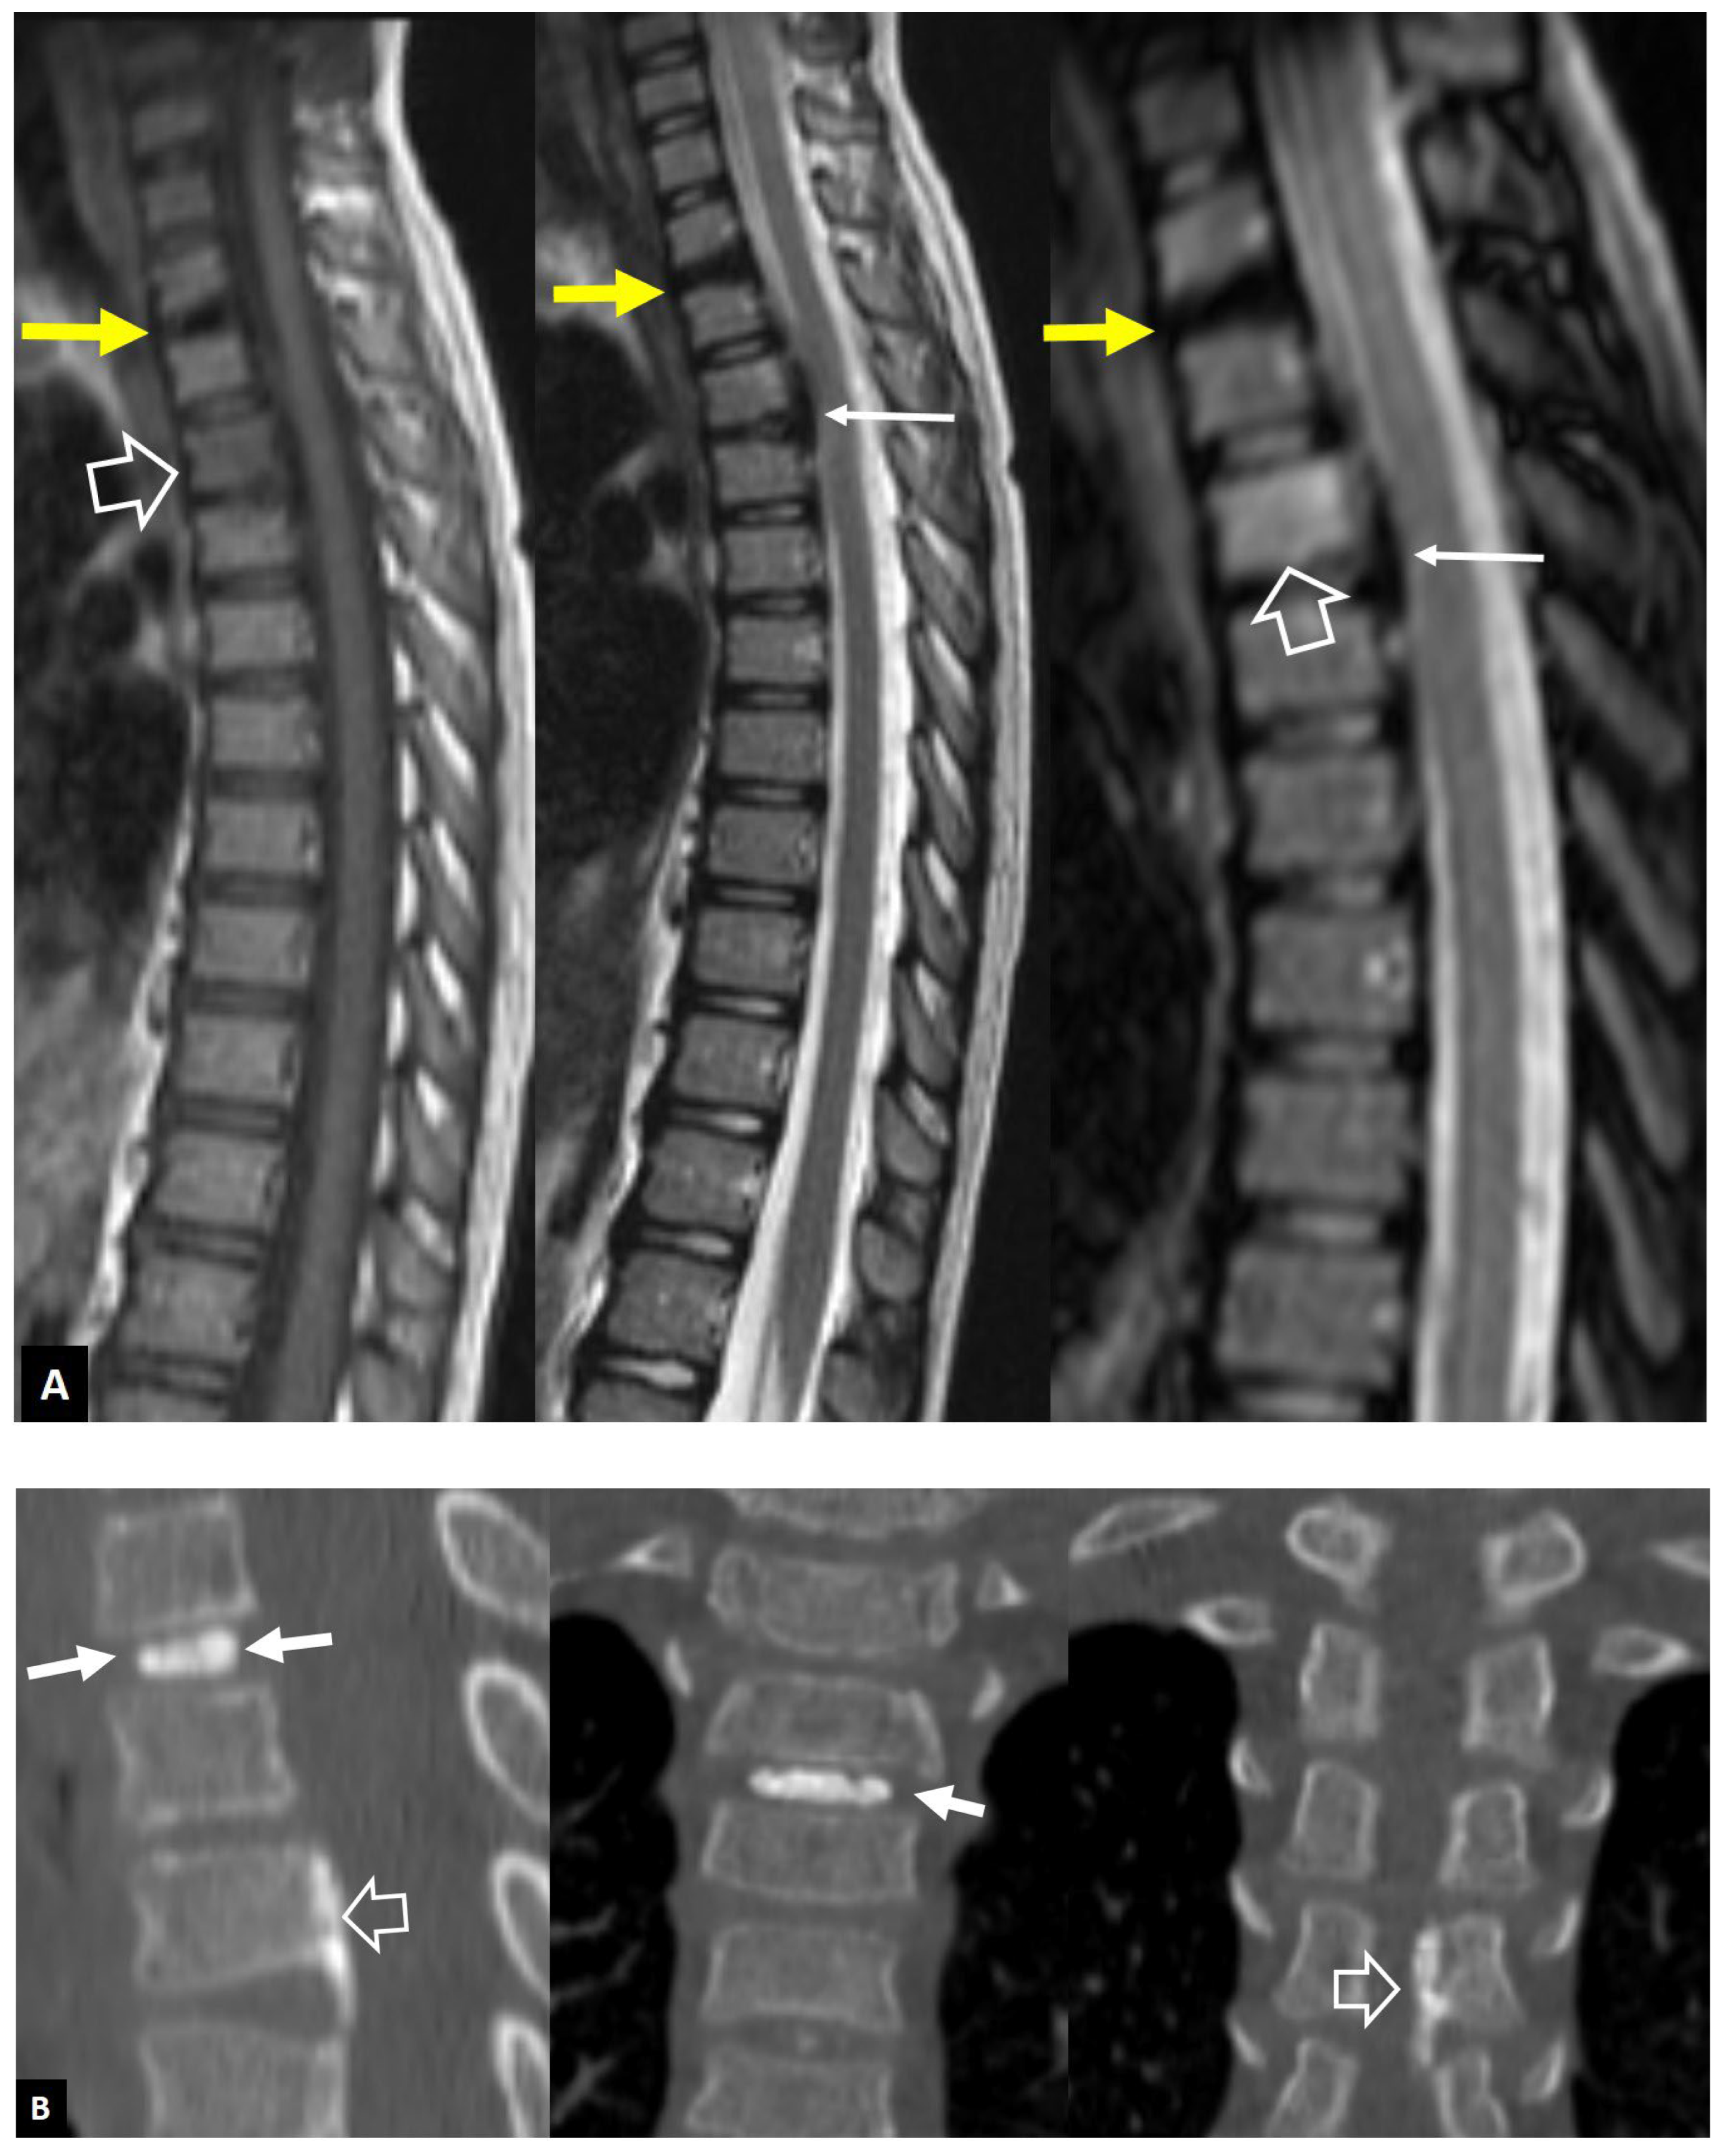

1. a.ii. Aseptic Spondylodiscitis

1. a.iii. SAPHO Syndrome

1. a.iv. Destructive Spondyloarthropathy